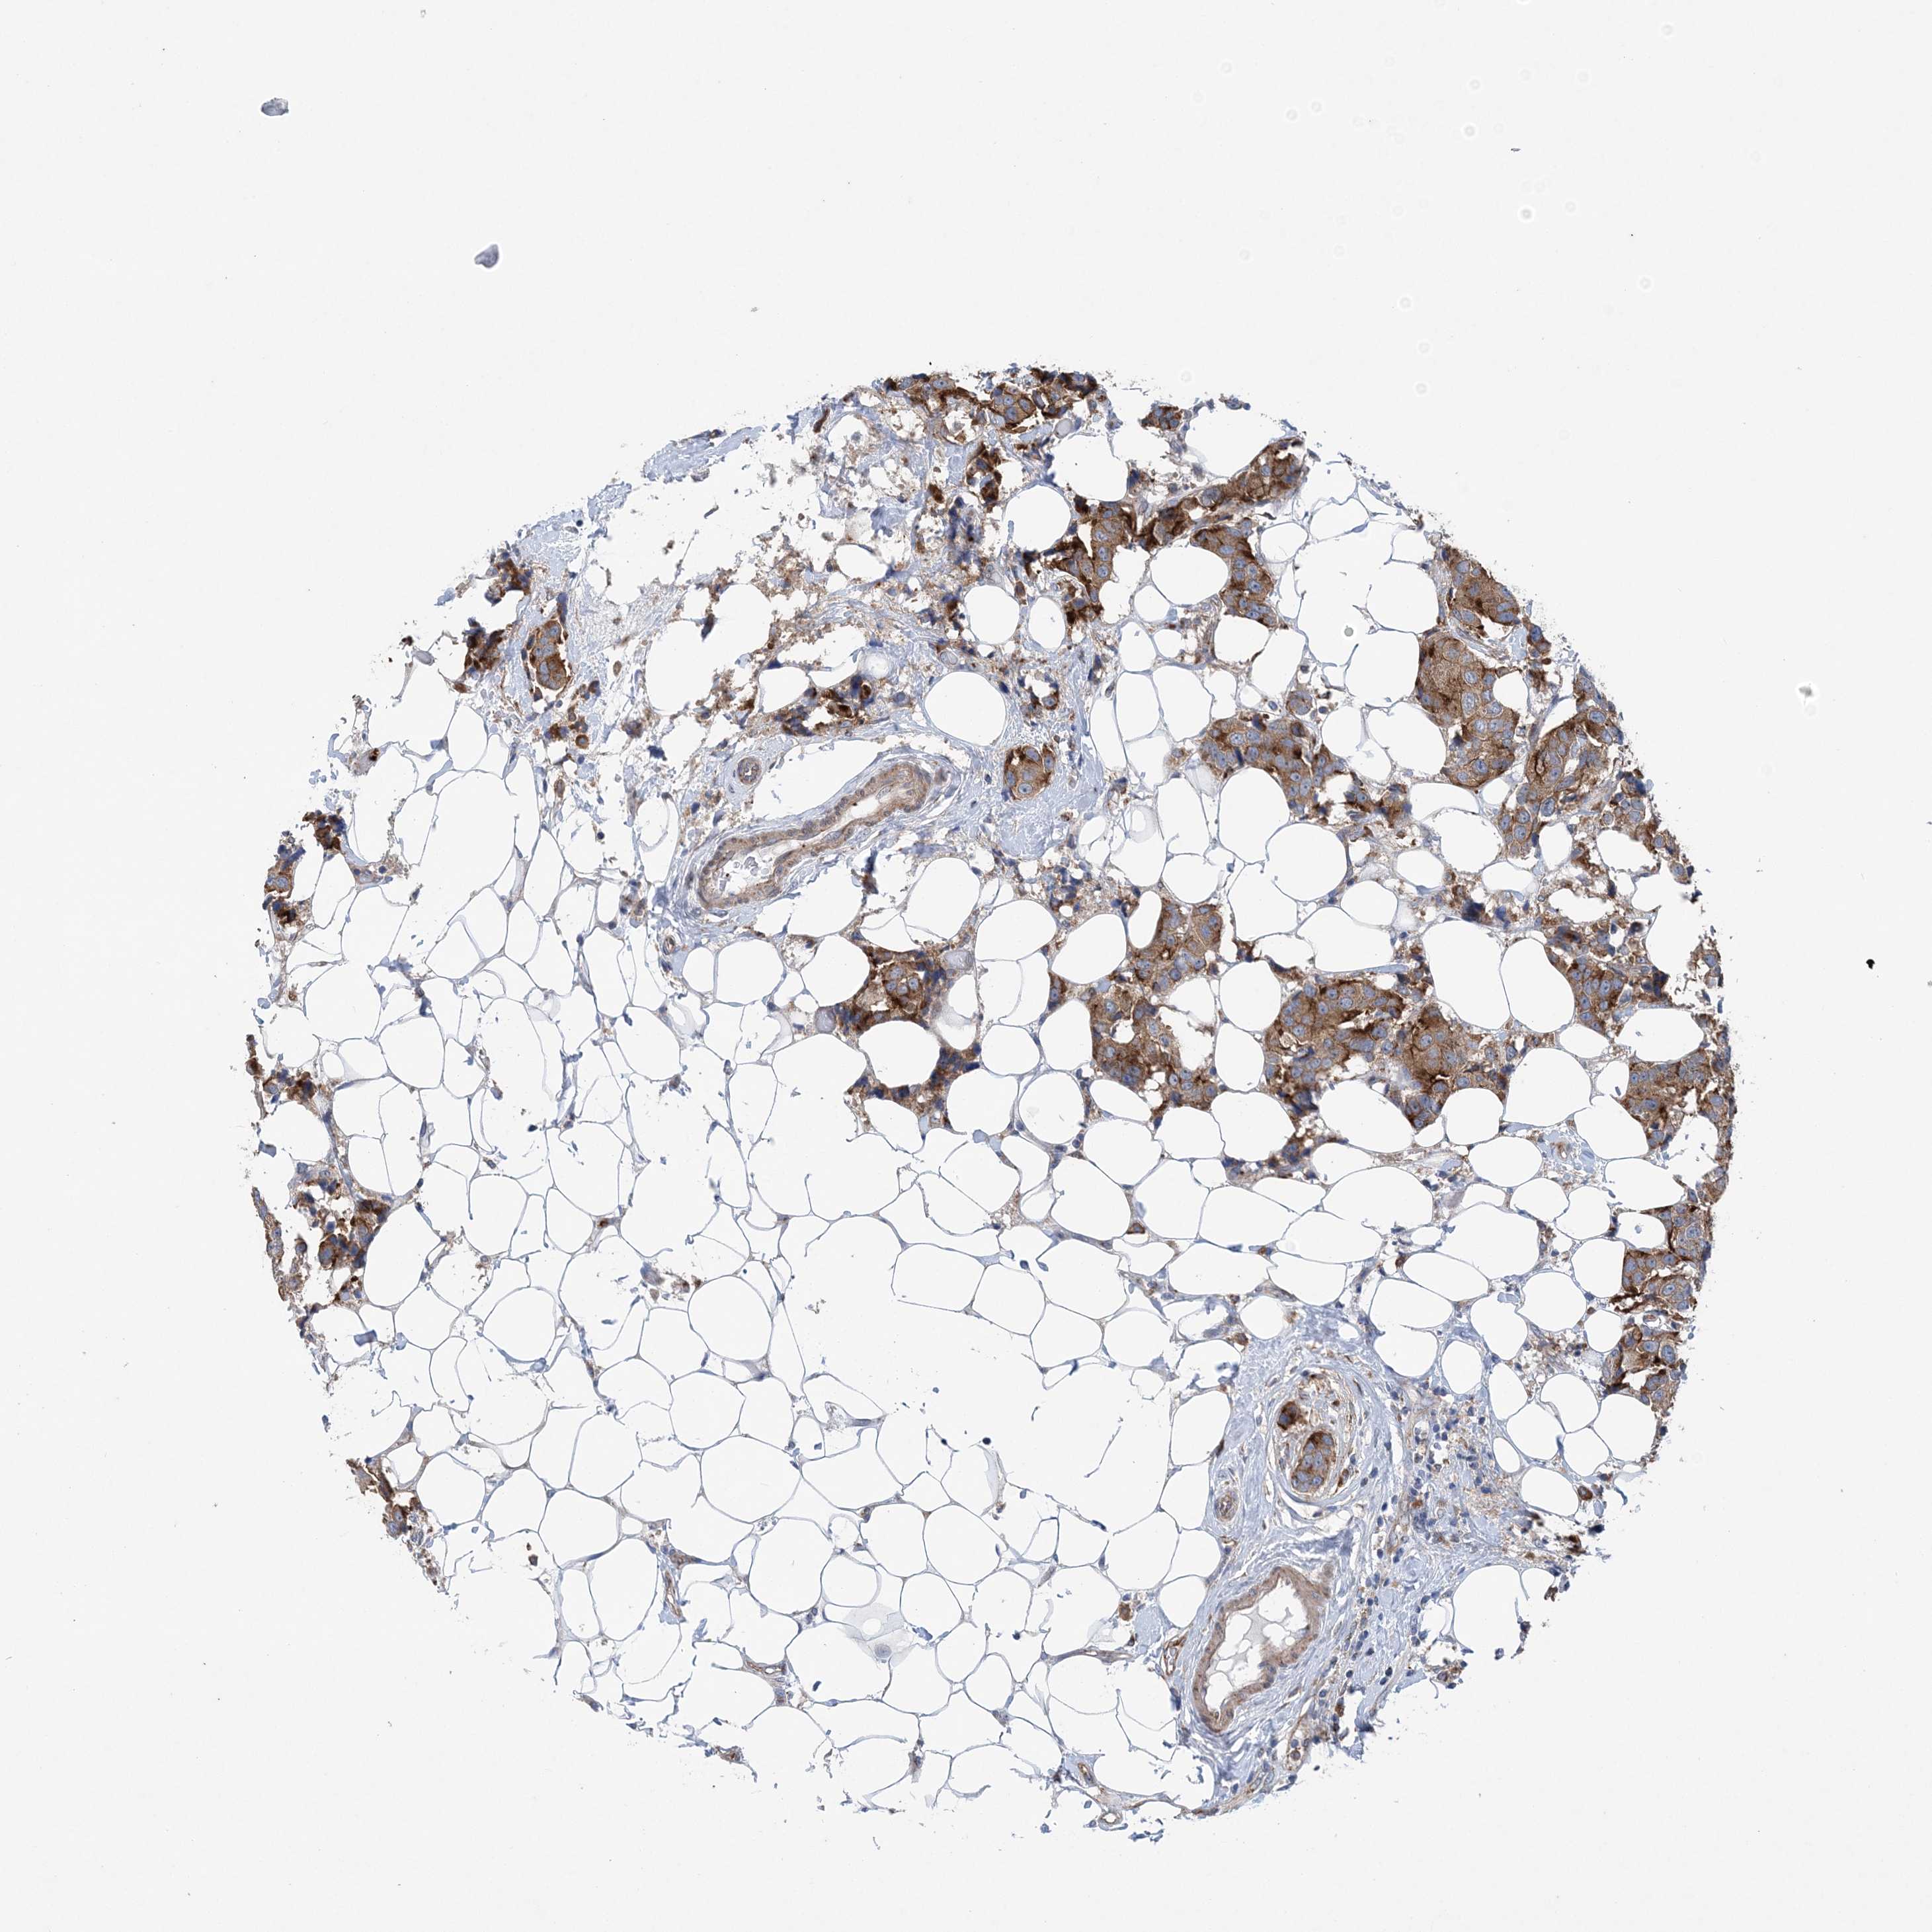

BRCA TCGA BRCA VALIDATION PROTEIN EXPRESSION